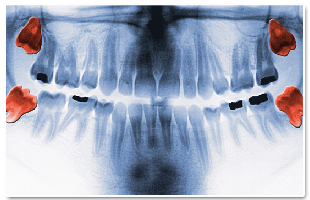

Impacted Teeth

Impacted Teeth.

The wisdom teeth cannot find place on the jaw as they are the last to come out, so that, they usually remain embedded.